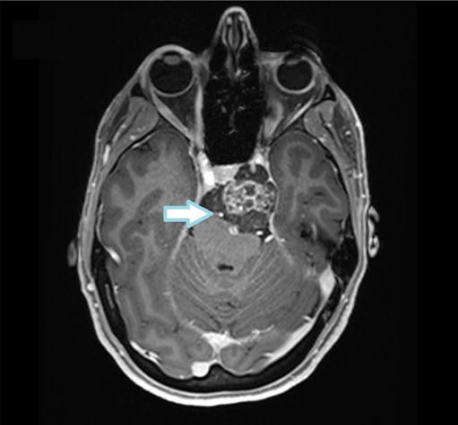

38岁女性,斜坡脊索瘤,位于颅底的重要区域,其生长方式特殊,紧紧包裹着基底动脉以及左大脑后动脉。手术十分具有挑战性,因为基底动脉是大脑供血的关键血管,而左大脑后动脉则负责供应大脑半球后部的血液。因此,在考虑治疗方案时,医生必须格外小心,以确保在尽量移除肿瘤的同时,保护这些关键的血管不受损伤,以维持正常的脑部功能。

术前MRI显示上斜坡脊索瘤包裹基底动脉和左大脑后动脉

术后MRI显示近完全肿瘤切除(残留部分位于海绵窦水平)和通畅的血管(箭头所示)。